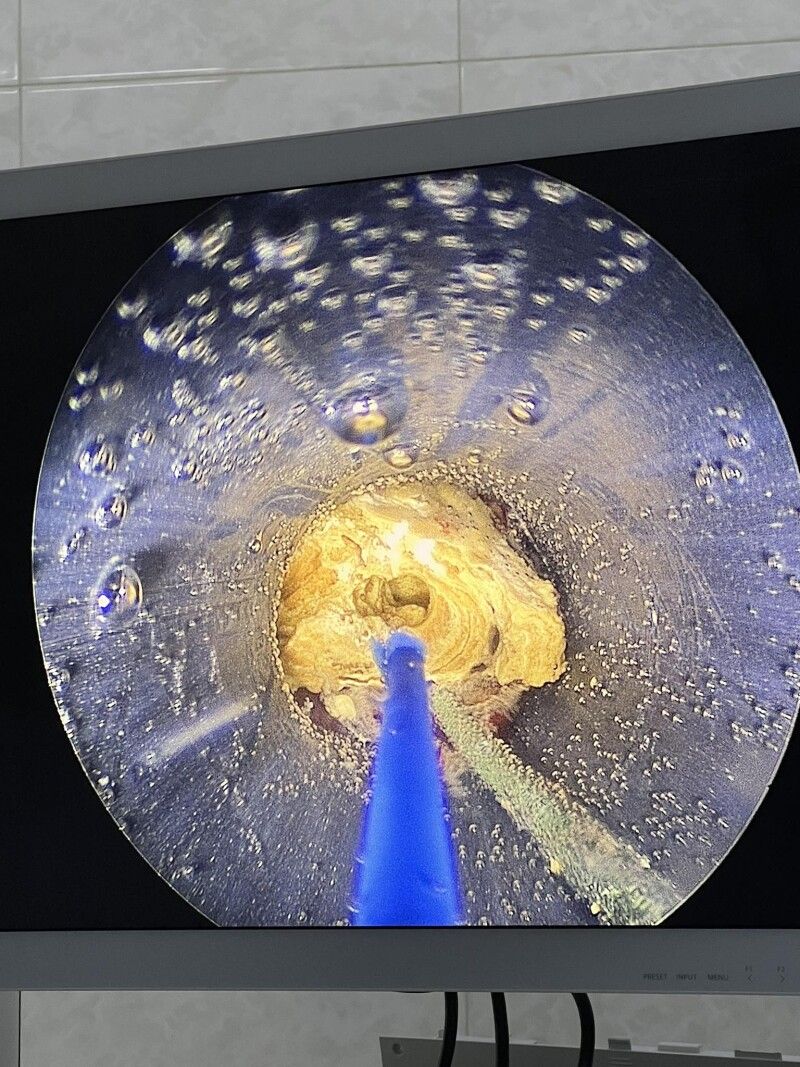

У Нововолинську виконали малоінвазивне ендоскопічне втручання під контролем сучасної візуалізації та з використанням лазерної системи Quanta System 60 W.

Конкремент фрагментовано і видалено через мінімальний перкутанний доступ, що забезпечує точну літотрипсію, мінімальну травму тканин та швидке відновлення.

- точна фрагментація каменю лазером;

- мінімальний розріз — лише 5 мм;

- знижений ризик післяопераційних ускладнень;

- швидка післяопераційна реабілітація.

Пацієнт уже наступного дня демонструє позитивну післяопераційну динаміку.